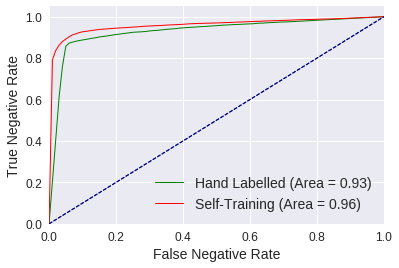

2) We empirically evaluate the ability of 3D-ConvNets [11] to detect anomalies using our initial dataset, observing average AUROC (Area Under the ROC Curve) scores of 0.94 and 0.93 for positive samples (containing anomalies) and negative (anomaly-free) samples, respectively. We also find evidence that excluding samples with motion blur improves classification accuracy.

4) Due to the small number of training samples the 3D-ConvNets over-fit after 100 epochs. To address this issue we use self-training (bootstrapping) for augmenting our dataset [30], incorporating the FC-GANs-based saliency maps into a multi-classifier voting system to automatically label additional training samples. Upon optimizing 3D-ConvNets using the additional samples we observe improved AUROC scores of 0.96 for positive and negative evaluation samples.

The ConvNets optimized with the self-training dataset significantly outperform those using only hand-labelled samples, as evident from the time-series plots depicted in the first row of Table 3. Furthermore, the frame range plots illustrating the mean cross entropy loss in the second row show a decrease in error across all evaluation sets. This translates to an increase in prediction accuracy for challenging rejects, achieving 85.1% between frame range 40 to 100. Furthermore, the overall accuracy for evaluation sets of 88.7% between frames 80 and 100 increases to 90.5%. Finally, we compute the AUROC for both approaches using samples between frame ranges 40 and 120. Self-training achieves an AUROC of 0.96 for positive and negative samples, compared to 0.94 and 0.93 when only using the hand-labelled dataset (see Figure 5). This evidence supports that disagreeing classifiers can be used under strict and lenient classification conditions, to automatically label and add samples to a dataset while providing sufficient sample variance for learning improved models.

2) Using this dataset we train ten randomly initialized 3D-ConvNets, where upon computing the AUROC we observe scores of 0.94 and 0.93 for positive (anomaly containing) and negative (anomaly-free) samples, respectively.

4) Given the small size of our dataset, we use self-training, automatically labelled 20-frame samples. To reduce the likelihood of noisy labels we use a voting system that also makes use of the FC-GANs based saliency maps to determine when classifiers are in agreement regarding an anomaly’s location. Classifiers trained with the augmented dataset achieve AUROC scores of 0.96 for both positive and negative samples, improving on the benchmarks set by 3D-ConvNets using our unaugmented dataset (See Table 3 and Figure 5).